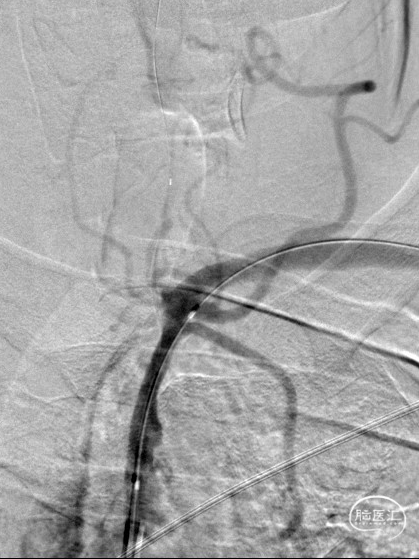

造影见LV闭塞,立即沿0.014*200cm 通桥北斗SS™神经血管导丝置入3mm*16mm 药物球扩支架至LV1。

压力泵逐渐加压球扩支架到8atm, 支架打开良好,造影示残余狭窄0%。

双侧锁骨下动脉造影见椎动脉、基底动脉血流通畅,远端未见栓塞表现。